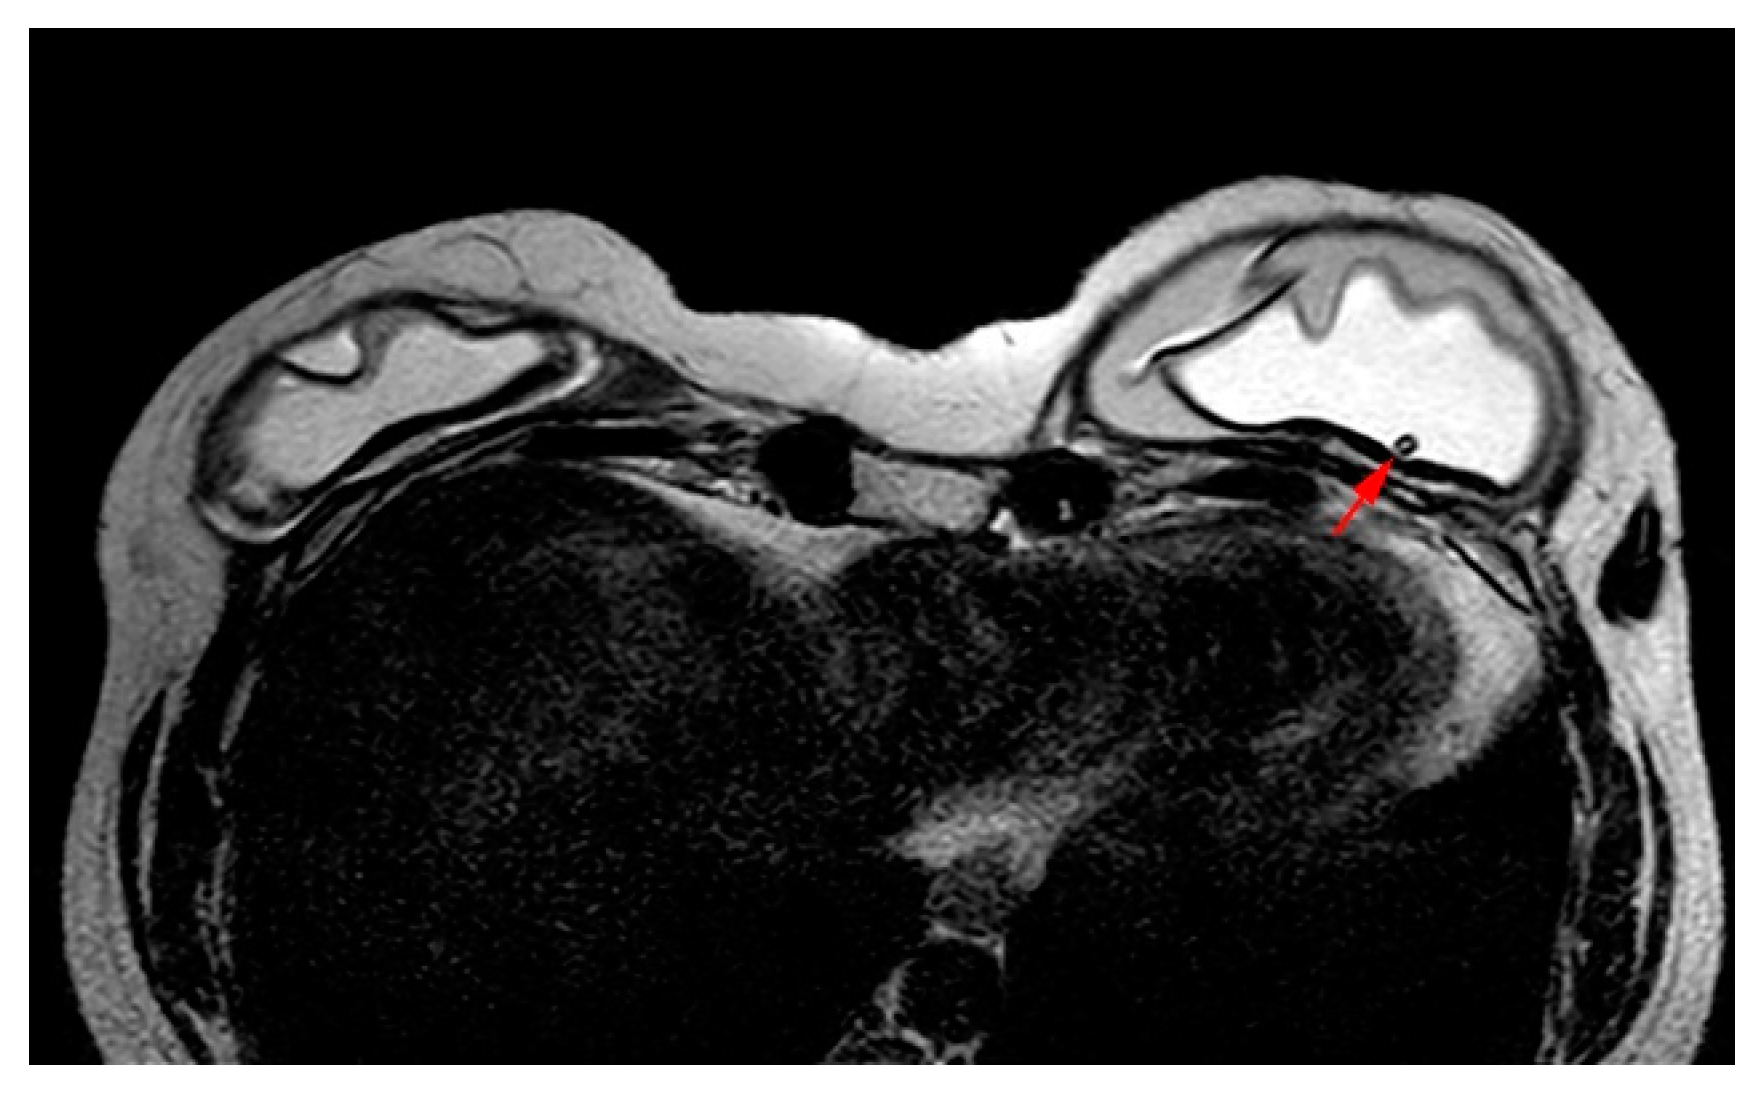

The pedicled or free TRAM flap and the LD flap consist of the rectus abdominis and latissimus dorsi muscle respectively and also the overlying skin and subcutaneous fat. In the TRAM reconstruction the flap is recognized centrally along the anterior chest wall in axial images. In the LD reconstruction the flap is more eccentric with a tailed appearance of the muscle in the lateral breast as a result of the flipping and tunneling of the flap harvested from the back, differentiating it from a TRAM flap (Figure 2) [35]. In both cases the muscle atrophies over time. A thin low signal intensity curvilinear line parallel to the breast contour is often visible, best appreciated on sagittal images, representing the dermal layer of the lower abdominal or the dorsal wall [35,45]. The contact zone of the TRAM flap to the mastectomy site, that corresponds to the musculovascular pedicle may exhibit contrast enhancement [46].

Figure 2. Bilateral autologous Latissimus Dorsi (LD) reconstruction. Yellow arrows point the characteristic tailed aspect of the muscle. Red arrows depict a hypointense circumscribed area with irregular wall enhancement and associated solid enhancing nodule corresponding to a local relapse of high grade invasive ductal carcinoma, triple negative, with marked central necrosis.